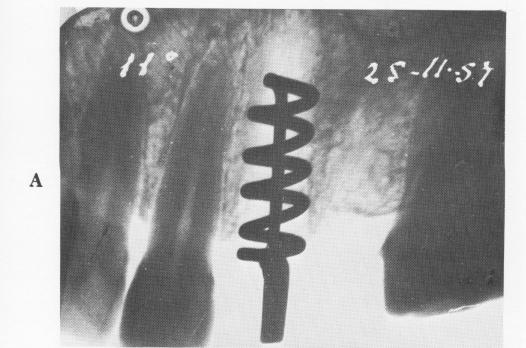

distance between them, that was important, Perron-Andres fairly consistently fashioned implants that could not be set deeply enough to avoid invagination problems. His skill in fashioning, inserting, and stabilizing an implant can be seen in Fig. 5-33. Even though the uppermost spires are not embedded in bone, the thick condensation of bone around the lower spirals is obvious. At the time of the last x-rays, the implant had been in place 3 years.

Fig. 5-33. A, Perron-Andres screw inserted into an open socket. B, Thirty-six months later, bone is seen closely adapted to and through the spirals.

1 Perron-Andres endosseous implant inserted in open socket in maxilla

2 Perron-Andres endosseous implant with bone adaptation in maxilla